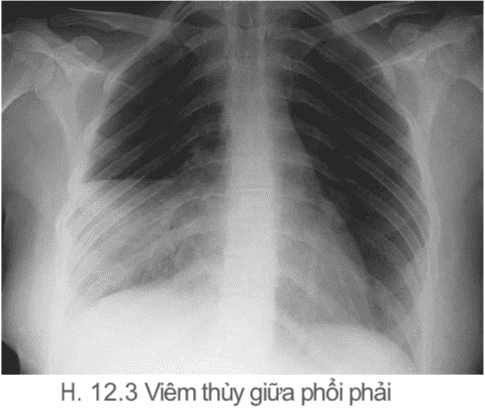

- Viêm đáy phổi nếu có bằng chứng lâm sàng hoặc xquang của đông đặc đáy phổi đặc biệt nếu kèm ho có đàm hoặc khó thở.